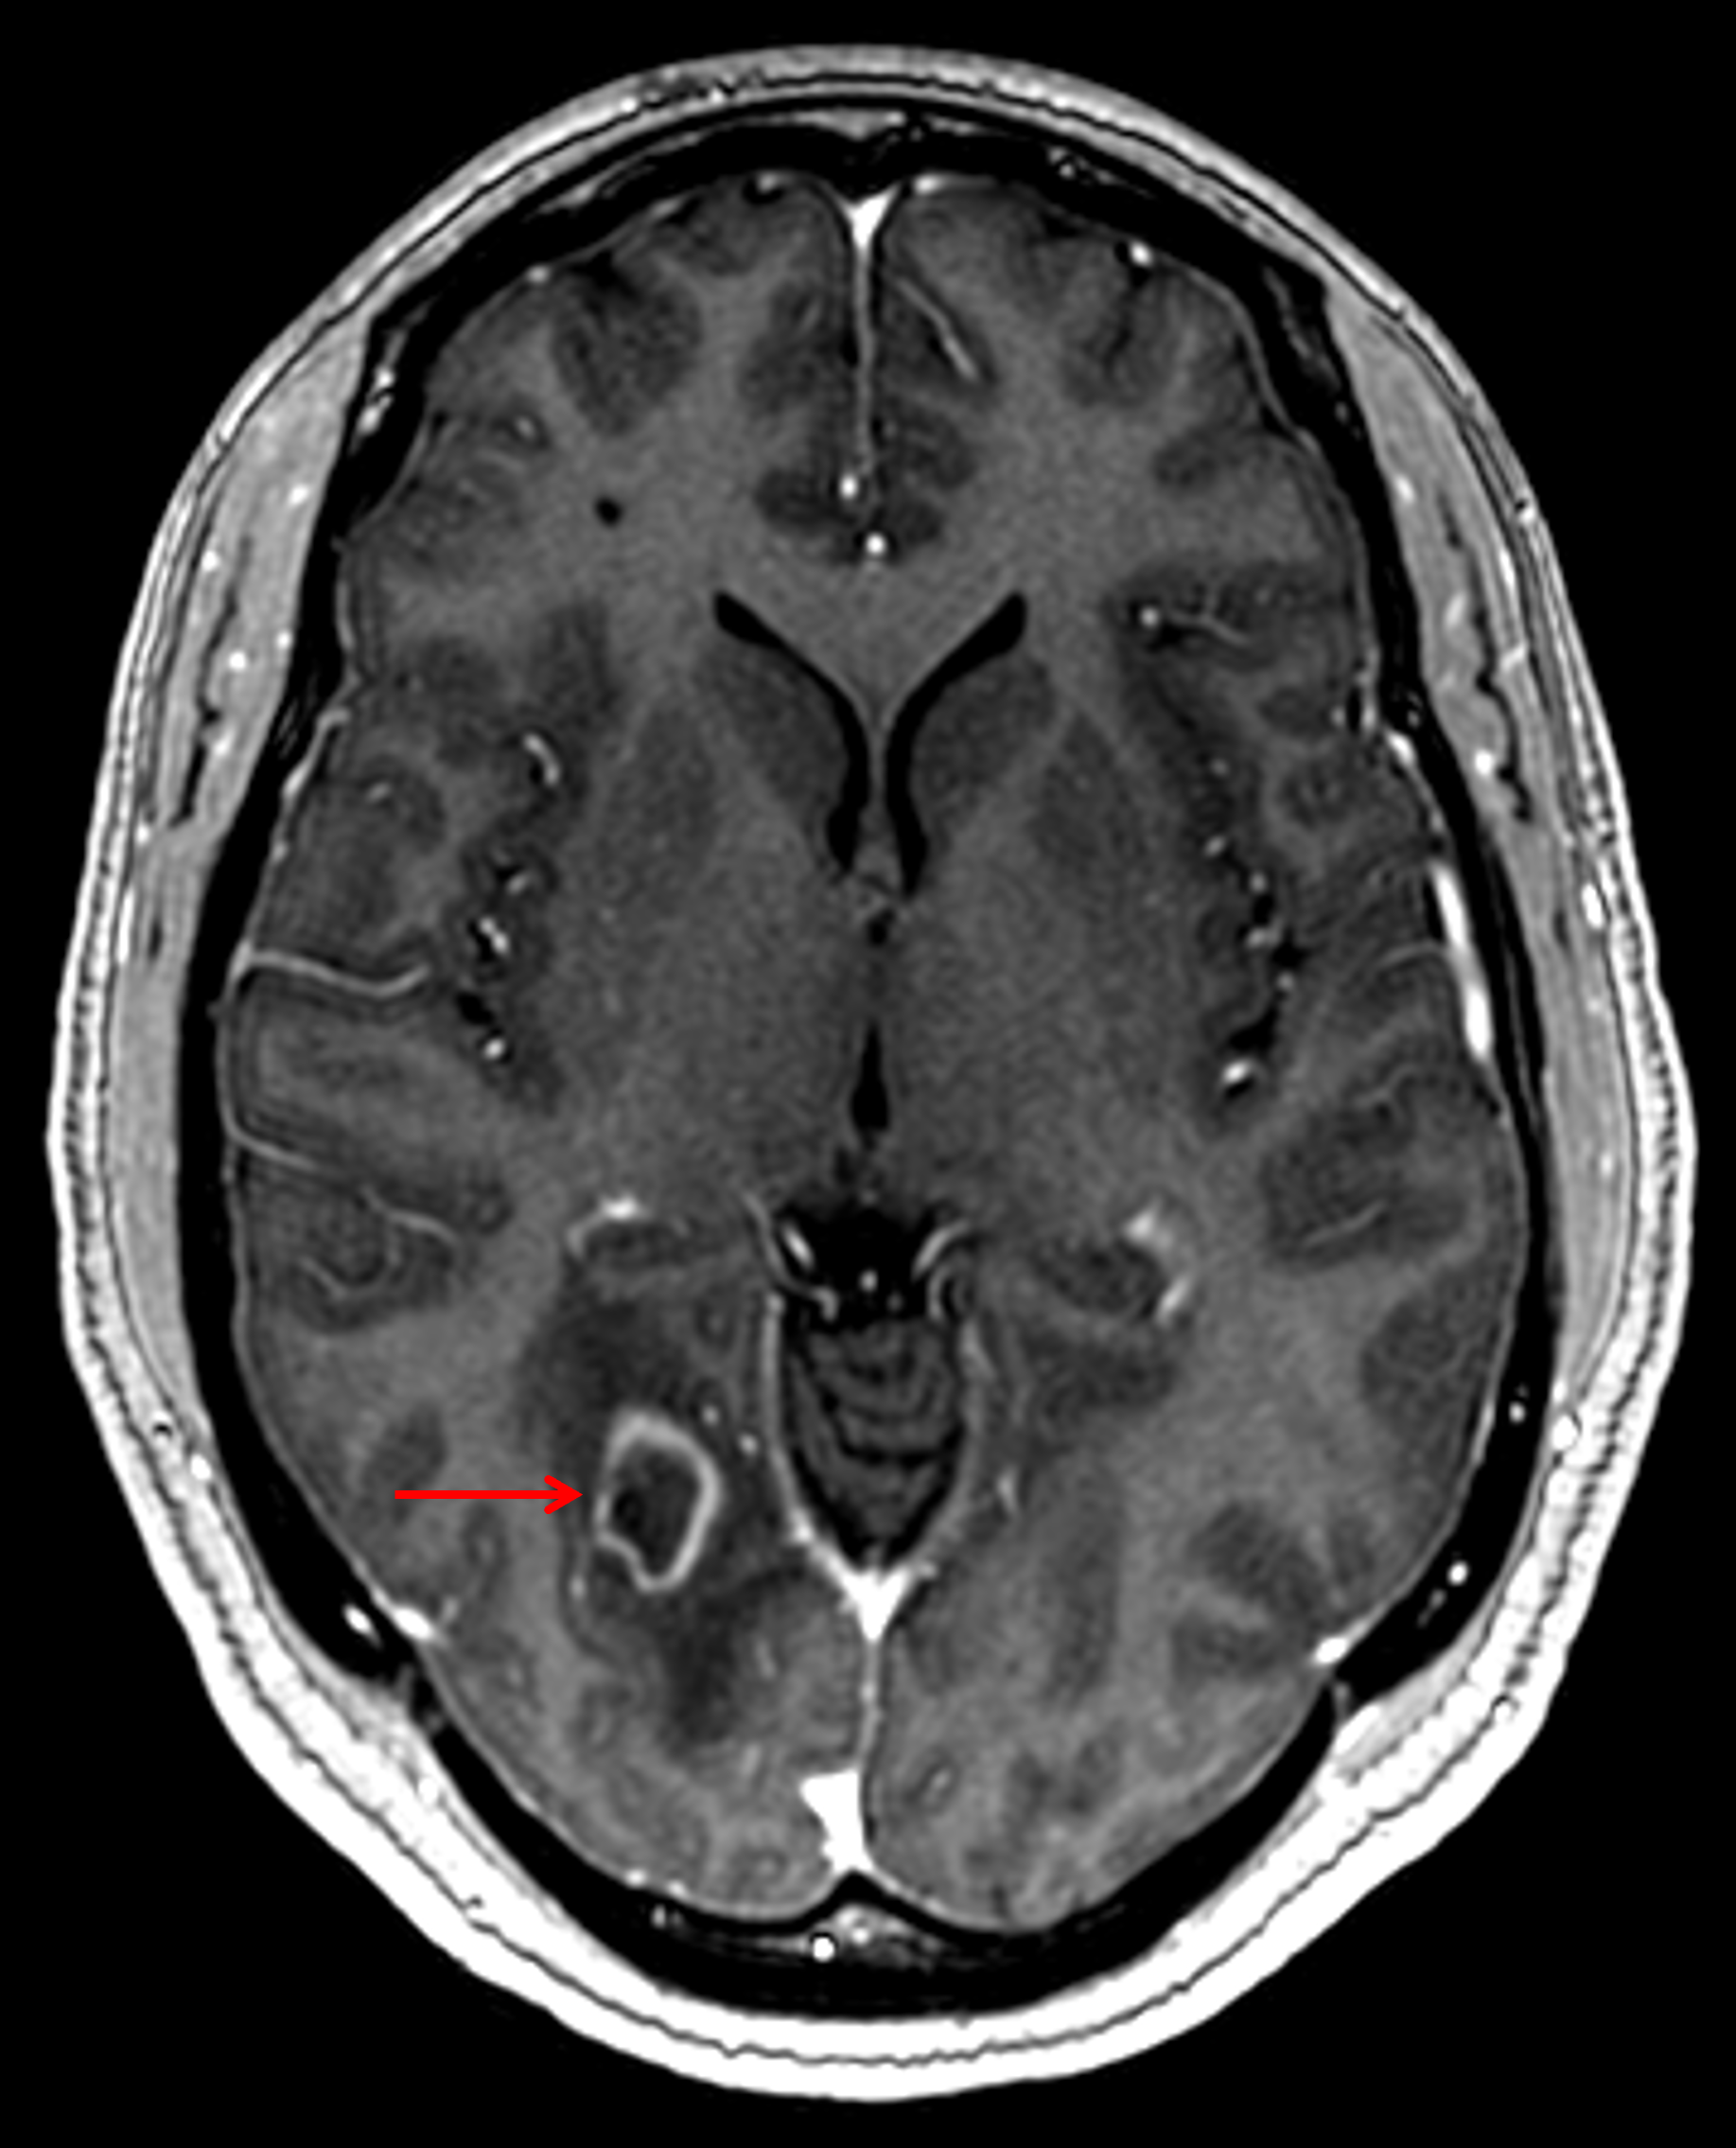

Age: 34

Sex: Female

Indication: Headache, history of HIV/AIDS

CNS toxoplasmosis